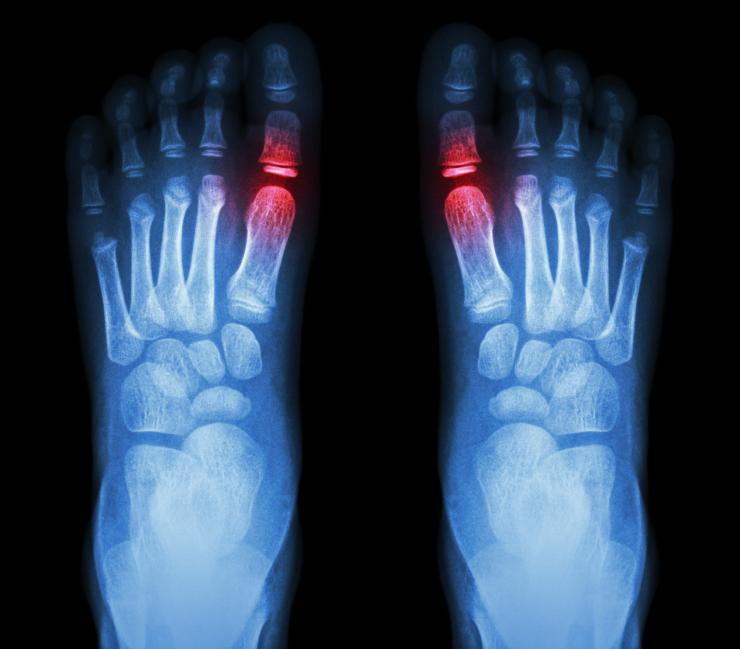

La gota o los ataques de gota se producen cuando la acumulación de cristales de urato —derivada de los altos niveles de ácido úrico en sangre— provoca la inflamación e hinchazón de las articulaciones. Así pues, las partes del cuerpo que más afectadas se ven son: el dedo gordo del pie (uno o ambos), las rodillas, los tobillos, los codos, etc.

• enrojecimiento de la articulación afectada